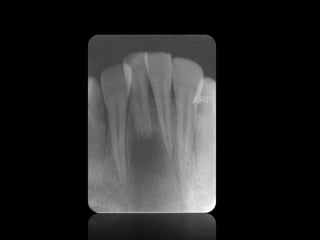

REABSORCIÓN DENTAL EXTERNA

REABSORCIÓN DENTAL INTERNA